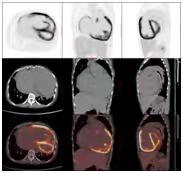

医师决定行二尖瓣机械瓣置换术(保留瓣下结构),三尖瓣成形术,房间隔缺损人造补片修补术,动脉导管未闭切段缝合术。术前为排外手术禁忌证,2022.11行PET/CT示:巨大心脏显影,房室各壁心肌代谢明显增高。

(图1)先天性心脏病患者(女,41岁)18F-FDG PET/CT显像图。1A.全身最大密度投影图示心脏明显扩大,房室各壁糖代谢明显增高;2B.心脏断层显像示各室壁糖代谢明显增高,SUVmax为11.5;1C.横断面、冠状面、矢状面三个不同层面示心腔明显增大,各室壁糖代谢明显增高。图2同一患者胸片。2A.2022年10月(手术前)胸片:心胸比为0.88;2B.2022年12月(手术后)胸片:心胸比例为0.76。